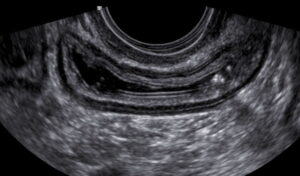

Ultrassom transvaginal com preparo intestinal mostrando a estratificação de uma alça intestinal normal.